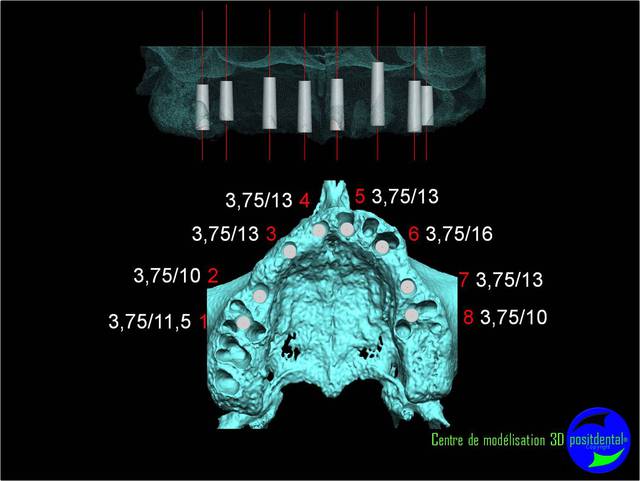

planif cas 1

Si tu as suivi les cas présentés depuis plusieurs années les bridges provisoires ont une armature métal pour la rigidité du fixateur externe, l’intervention se déroule en 1 seul temps chirurgical donc sans prise d’empreinte, c’est pour cela que je parle de MCI. Pour la passivité du bridge avec le système Nobel Guide et leurs piliers expansifs je n’ai vue aucun cas clinique présenté sur le forum. As-tu déjà utilisé le procédé ? Dans les cas présentés sur la vidéo, aucune clé de positionnement n’a été utilisée, le placement des piliers se fait selon la simulation implantaire assistée par ordinateur, leurs présentations a été faite en prospective par OTP, modèle 3D et à la demande de beotien la solution pilier fixe a été retenu à la place du bridge transvisé. Quel sont les compléments d’information que tu as besoin et ou la photo ne te suffi pas ? Pour le protocole d’une MCI, empreintes des maxillaires, dimension verticale de l’occlusion, définition de l’esthétique souhaitée, prescriptions, réalisation du Positscan, traitement des informations à partir des données DICOM, simulation implantaire assistée par ordinateur, validation, réception des DMSM selon les types d’implants et encastillages les procédures varient. Quel système implantaire utilise-tu ?